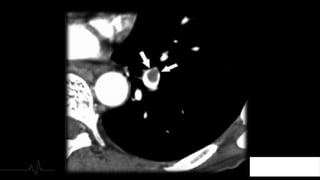

2. TIPO DE TROMBO

Trombos Agudos

Localizados - centro

de la luz del vaso

Provocan dilatación Ocupan la totalidad de

la luz

Paso de contraste en

la periferia

Trombo rodeado de

contraste

(Signo de tranvía) Localización

excéntrica

Presentan ángulo

agudo con la luz del

vaso

Localización en elvaso Morfología Ángulo con respecto a la luz 2. TIPO DE TROMBO

Trombos Agudos Localizados -centro de la luz del vaso Provocan dilatación Ocupan la totalidad de la luz Paso de contraste en la periferia Trombo rodeado de contraste (Signo de tranvía) Localización excéntrica Presentan ángulo agudo con la luz del vaso